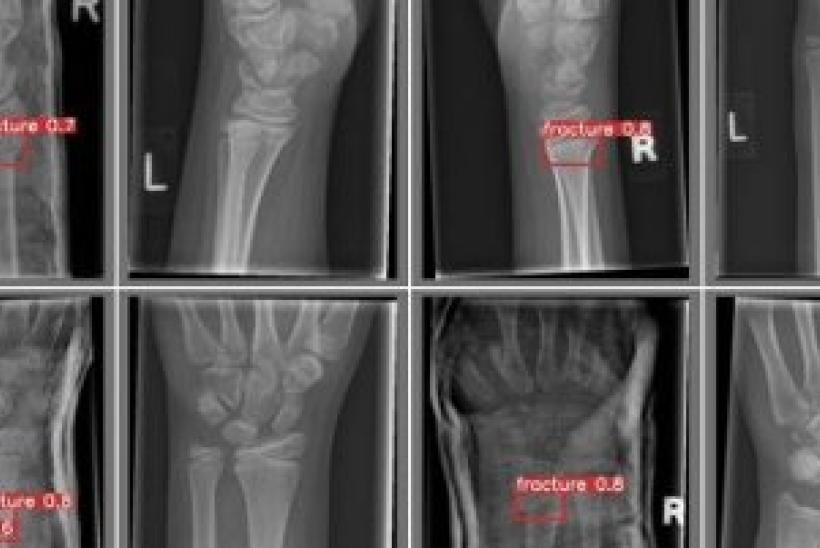

For specific questions asked about radiology, young people felt that AI would be accurate at finding problems on bone X-rays and they didn’t mind how long the results took, as long as they were as accurate as possible and that the AI was used with a trusted doctor still in charge of their care.

The study's findings are already being incorporated into cutting edge research based at GOSH, evaluating and developing AI tools to better detect and describe fractures from a large dataset of x-ray scans in children across Britain. Find out more about the FRACTURE Study here.